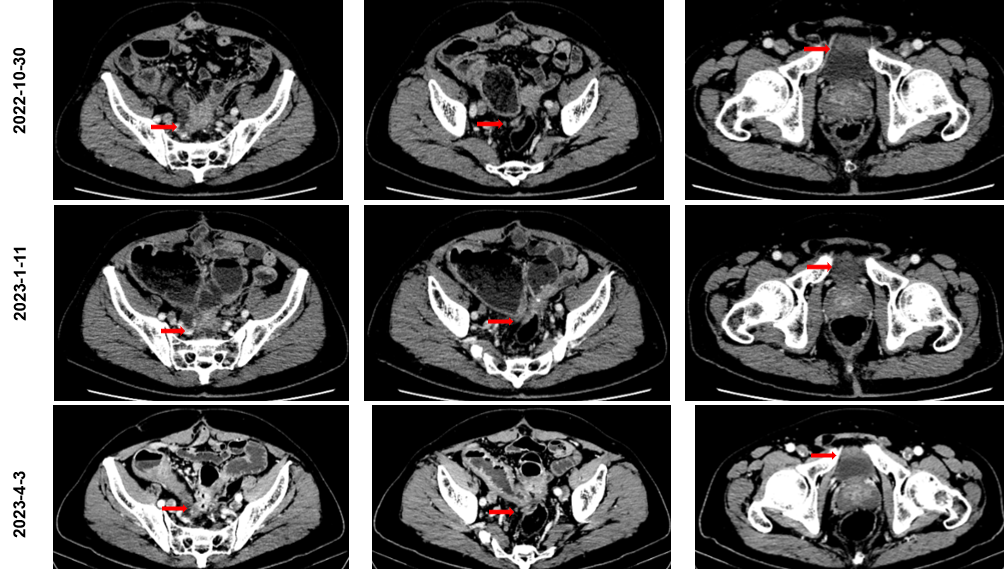

骶前区小片软组织密度灶,边界不清;紧邻上述病灶腹膜返折处见软组织结节,范围约1.3 cm×0.7 cm,强化欠均。膀胱左前方见范围约2.2 cm×1.3 cm软组织灶,增强后中等度强化,病灶粘连前腹壁及膀胱壁。

三线治疗:

骶前区小片软组织密度灶,范围约5.0 cm×3.3 cm,边界不清;紧邻上述病灶腹膜返折处见软组织结节,范围约1.6 cm×0.9 cm,强化欠均。膀胱左前方见范围约2.5 cm×1.8 cm软组织灶,增强后中等度强化,病灶粘连前腹壁及膀胱壁。

四线治疗:

2022年11月至2023年4月 行“TAS-102联合贝伐珠单抗”6周期(用法用量:TAS-102 60 mg bid;贝伐珠单抗 5 mg/ kg)。发生不全性肠梗阻症状3次,考虑癌性梗阻,给对症支持治疗好转。2023年1月至4月未再发生不全性肠梗阻。

2023年4月至11月 行“TAS-102联合贝伐珠单抗”14周期(用法用量:TAS-102 60 mg bid;贝伐 5 mg/ kg),未再发生不全性肠梗阻;患者自诉症状缓解明显,毒副作用低。

骶前区软组织灶,范围平扫密度不均,增强扫描欠均匀强化,边缘模糊,范围大致约4.3 cm×2.8 cm;乙状结肠吻合口壁增厚呈片状软组织灶,范围约4.1 cm×2.7 cm,与邻近小肠管壁粘连,并小肠壁增厚,周围脂肪间隙模糊;膀胱左前方见范围约3.3 cm×1.7 cm软组织灶,边界不清,病灶粘连膀胱壁。

梁仁佩教授:该患者的诊疗过程规范,经过手术、基因检测、介入及多线治疗后,目前OS已达到3年。患者四线应用TAS-102联合贝伐珠单抗后治疗效果较好,且未再出现肠梗阻,肿瘤标志物明显下降,肿瘤负荷减小,生活质量提升。目前结直肠癌治疗进入靶免时代,合理排兵布阵、推行MDT帮助治疗获益最大化。